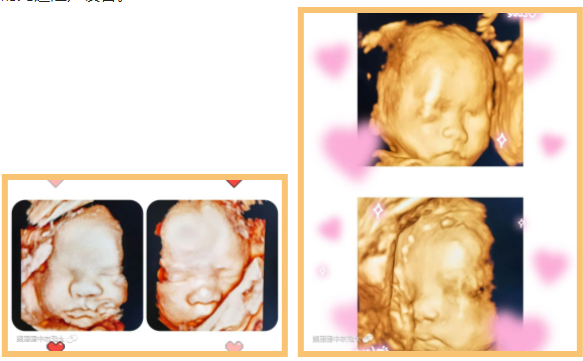

近日,超声医学科通过四维彩超筛查,为一位准妈妈做出了及时准确的胎儿发育健康提示。该孕妇为第一次妊娠,孕22周,既往超声检查结果未报异常,无创DNA结果低风险。在超声医学科进行胎儿系统筛查时,当日值班医生、超声医学科副主任王双艳,第一眼便发现胎儿头部形态异常并伴有侧脑室明显扩张,提示胎儿脑积水,考虑胎儿存在神经管畸形。经过一番认真细致的检查,发现胎儿除脑积水外,还有开放性脊柱裂、双足内翻,出现足内翻提示胎儿神经系统已经受损害。

(四维成像,结构异常更清晰)